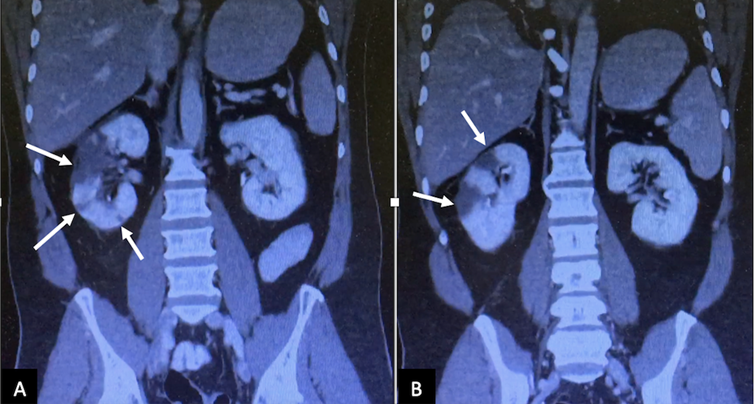

On 08/19, the patient reported abdominal distension with decreased bowel sounds, diffusely painful on deep palpation, not peritoneal. Oral tolerance is suspended, and a nasogastric tube is placed without gagging or vomiting. An abdomen-pelvis CT scan is requested, informing the proximal/middle third of the right renal artery, with images of lack of filling in its interior, and hypodense areas in the right kidney, of triangular morphology with a peripheral base, that are visualized during the contrasted phase consistent with renal infarcts (Fig. 2-3).

Coronal computed tomography image (A and B) in the nephrogenic phase showed multiple perfusion defects (arrows) in the right kidney, most pronounced in the upper pole, and lower pole too

Figure 2: Coronal computed tomography image